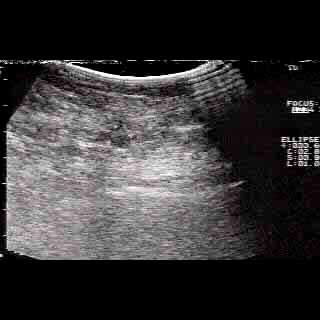

Οι απεικονίσεις των περιστατικών που επιδεικνύονται παρακάτω, έγιναν με κυρτές κεφαλές 3,5 και 5 ΜΗΖ, προκειμένου να φανεί, ότι και με τον εξοπλισμό αυτό, που σιγά-σιγά διαθέτουν όλο και περισσότερα ιατρεία, είμαστε σε θέση να έχουμε ικανοποιητικά αποτελέσματα.

Oι τελευταίες 4 απεικονίσεις έγιναν με ειδικό για μαστό ηχοβολέα linear, εναλλασσομένης συχνότητος 7,5-10ΜΗΖ.